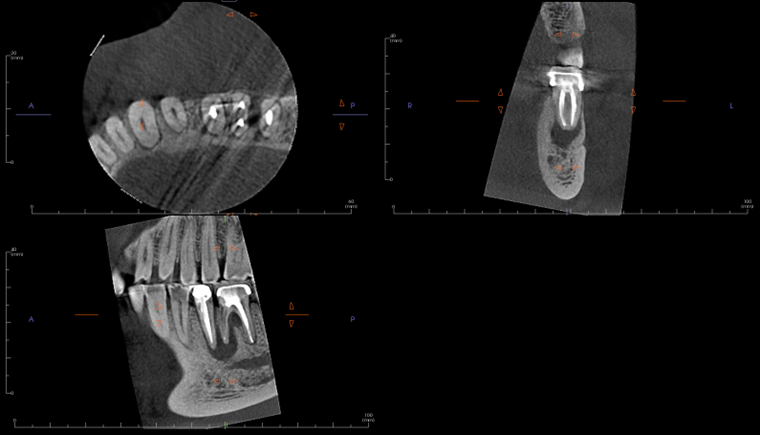

Radiographic evaluation: Periapical and bitewing radiographs of the mandibular left posterior quadrant show existing PFM crowns and prior root canal therapy on teeth #20 and #19, with a small, nonretentive post on #20. A large periapical radiolucency is noted at the M root of #19 which is confluent with a secondary large radiolucency at #20. The radiolucency on the M root of #19 extends towards the furcation.

A limited FOV CBCT was exposed revealing an area of low density encompassing the root apices of #19 and #20. There was no evidence of missed/non-negotiated secondary anatomy. Existing root fills are greater than 0.5mm from the radiographic apex. The areas of reduced radiographic density are consistent with the appearance of apical periodontitis, and are not in close proximity to the inferior alveolar nerve.

Treatment Rendered: Sometimes we have the opportunity to combine multiple treatment strategies in complex cases. In this case, non-surgical retreatment of #8 was performed in tandem with decompression. After discussing his treatment plan with the referring GD, the patient was seen first by his GD for removal of the existing crown and placement of a long-term milled temporary crown. The patient then returned to our office for the post and gutta-percha removal with placement of intracanal calcium hydroxide. This was followed by immediate decompression of the lesion. The decompression technique used was the simultaneous needle aspiration and irrigation method described by Hoen et al. (JOE, 1990). This involves placement of two 16 gauge needles into the lesion with simultaneous aspiration and irrigation with saline (no long-term drain was used). 30ml of saline was used to irrigate the lesion until the aspirated fluid was clear.

After one month, the patient returned for follow-up and the buccal sinus was still present. The tooth was re-accessed and the calcium hydroxide was replaced. At the two month mark, the buccal sinus tract was healed, but the canal still had continued mild drainage internally. A third round of calcium hydroxide was applied and left in place for 3 months. When the patient returned (5 months after initiating treatment), evidence of healing was observed radiographically around #7 and #8. RCT #8 was completed with an MTA obturation and RMGI orifice barrier. Sufficient ferrule and peripheral tooth structure was present and another post was considered not necessary.

After 2 months of calcium hydroxide. Early evidence of periapical healing, The buccal sinus tract healed but the canal was still draining internally. PA taken immediately after third round of calcium hydroxide (powder) applied.

Immediate Post-op (after long-term CaOH for 5 months)

6-month recall: Tooth #8 was asymptomatic and with no buccal sinus tract present. Tooth #7 remains responsive to cold testing. The patient had not returned to their GD for the permanent crown. The mobility in #8 was notably reduced and significant healing was observed radiographically. The lesion may heal with an apical scar, but apical surgery will likely not be necessary. The patient was scheduled for a 12-month recall and advised to return to their GD soon for the permanent crown.